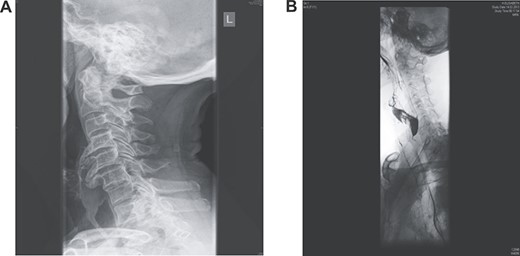

Her past history included right knee joint arthroplasty. There were no neurological manifestations, and there was no history of neck pain or trauma. The findings on physical examination were unremarkable. The routine blood test results were within the normal range. Oesophagoscopy revealed luminal stenosis by external compression on the posterior hypopharynx/oesophageal wall with no tumour or diverticula. Lateral neck X-ray and computed tomography (CT) examinations showed a giant anterior multilevel osteophytic formation spanning C4/5/6 and compressing the oesophagus, with no ossification of the anterior longitudinal ligament (Fig. 1A). A gastrografin swallow showed that osteophytes were severely protruding and impinging on the oesophagus, with partial obstruction (Fig. 1B).

(A) Lateral X-ray reveals giant multilevel osteophytes at C4/5/6 compressing the oesophagus; (B) a gastrografin swallow showed that osteophytes were severely protruding impinging on the oesophagus with partial obstruction.